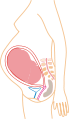

Third trimester

Final weight gain takes place, and the fetus begins to move regularly. The woman's navel will sometimes become convex, "popping" out, due to her expanding abdomen. This period of her pregnancy can be uncomfortable, causing symptoms like weak bladder control and back-ache. Movement of the fetus becomes stronger and more frequent and via improved brain, eye, and muscle function the fetus is prepared for ex utero viability. The woman can feel the fetus "rolling" and it may cause pain or discomfort when it is near the woman's ribs and spine.

It is during this time that a baby born prematurely may survive. The use of modern medical intensive care technology has greatly increased the probability of premature babies surviving, and has pushed back the boundary of viability to much earlier dates than would be possible without assistance. In spite of these developments, premature birth remains a major threat to the fetus, and may result in ill-health in later life, even if the baby survives.